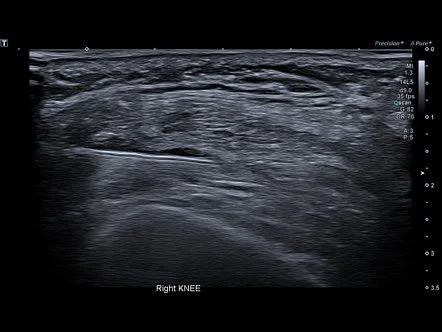

Echogeleide injectie

Knie